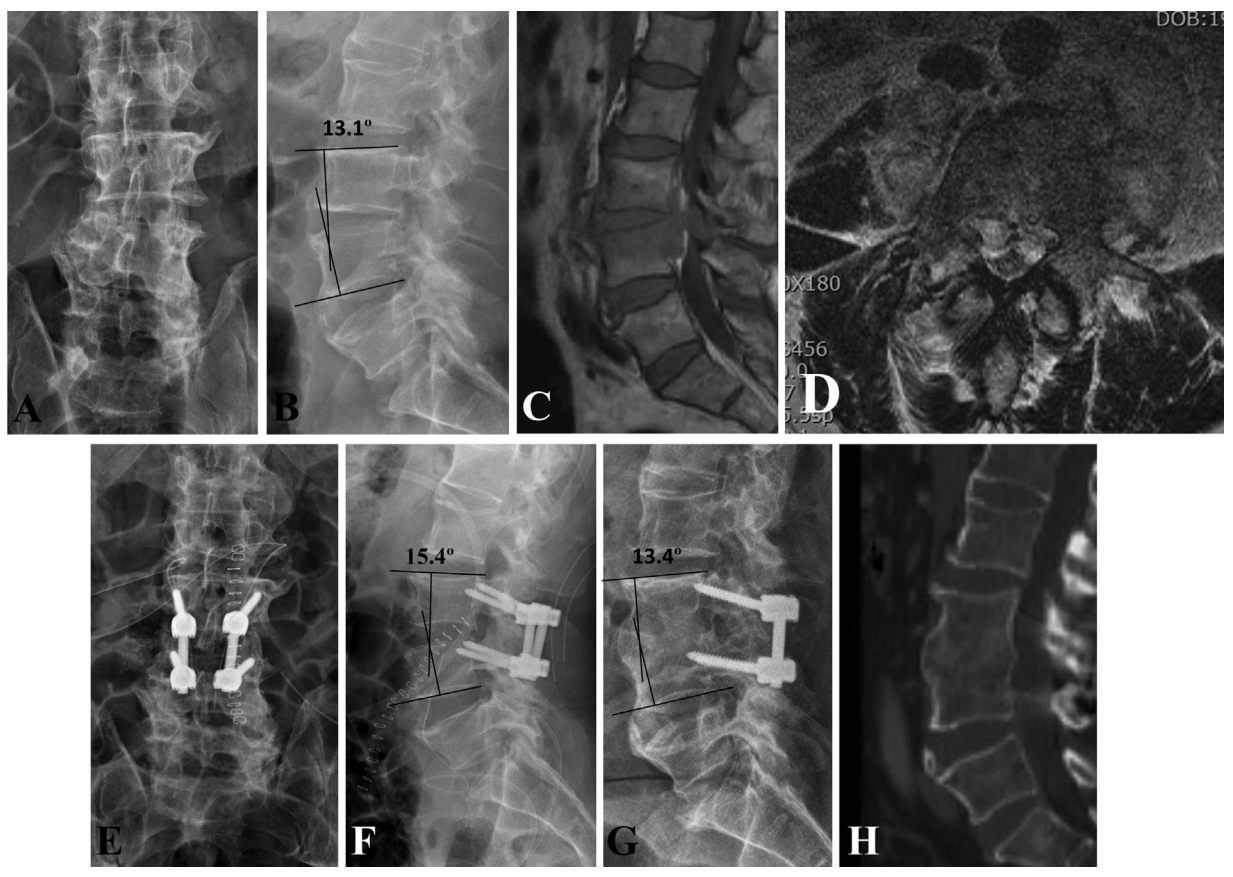

图1: 55岁L3-L4化脓性脊柱炎男性患者。主因“腰痛、双下肢放射痛,发热7天”入院,已在门诊保守治疗4天。(A)正位(AP)和(B)侧位x线片。术前、术后及最后一次随访时畸形角度分别为13.1°、15.4°、13.4°。(C,D)磁共振成像(MRI)显示硬膜外和椎旁脓肿压迫脊神经,L3和L4椎体骨髓内信号改变。(E,F)手术和(G) 最后一次随访x线平片显示脊柱形态良好。(H)CT重建显示融合节段完全融合。